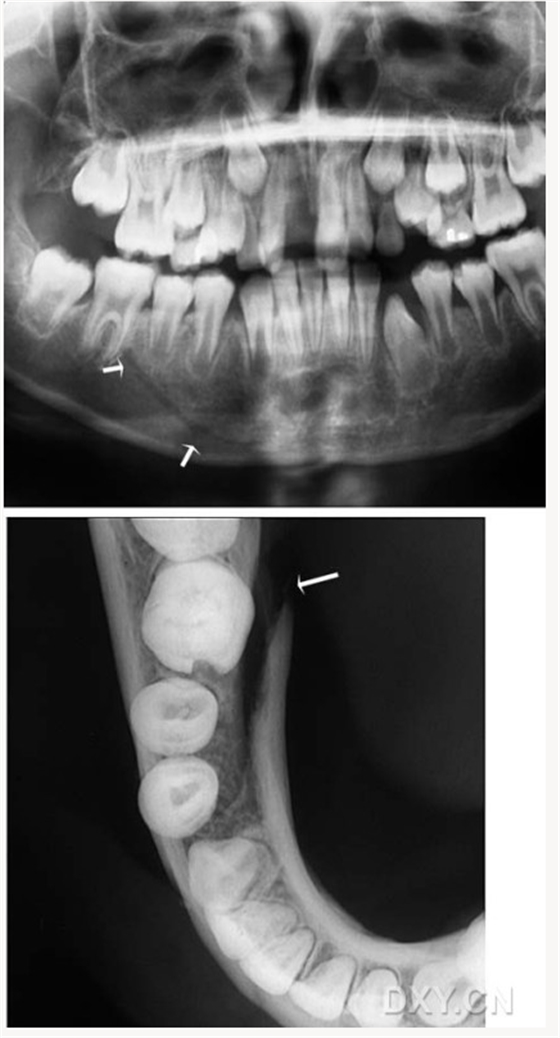

頜骨骨折